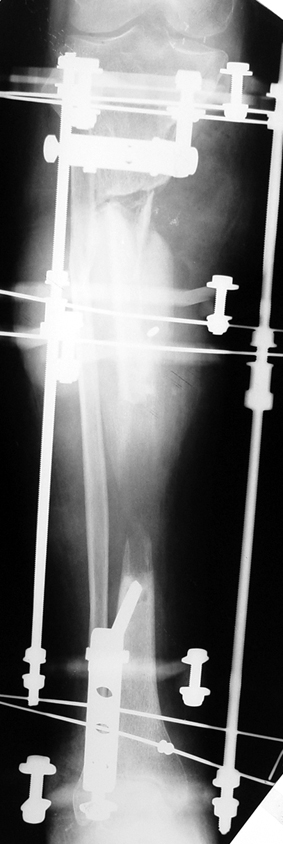

Recently, ilizarov techniques which is basis depend on distraction osteogenesis , bone segment transport or acute shortening after the resection at the site of pseudarthrosis combined with lengthening at another level of bone have been used. These treatment techniques may include some advantage for problems of infection, leg-length discrepancy, soft-tissue loss, and joint contracture.